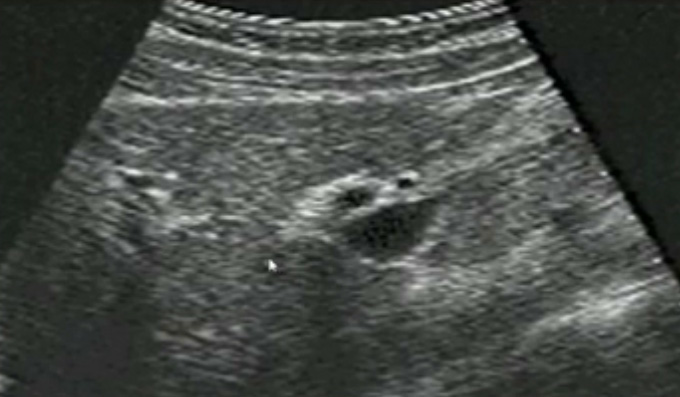

一、正常膽囊超聲圖像有的時候經(jīng)常發(fā)現(xiàn)檢查不到膽囊,其實有幾種可能性,檢查人員的技術(shù)不過關(guān)沒發(fā)現(xiàn)膽囊,就要找上級醫(yī)生會診,如果還是沒找到的話就不是技術(shù)問題。結(jié)石或腫瘤充滿膽囊,使其液腔消失,慢性膽囊炎使得膽囊萎縮或膽囊壁肥厚而囊腔消失患者已進食,膽囊處于膽汁排空的狀態(tài),膽囊先天性過小或缺失;膽囊位置極端異常(可能很低或位于左側(cè))膽囊切除術(shù)后(注意詢問病史)。